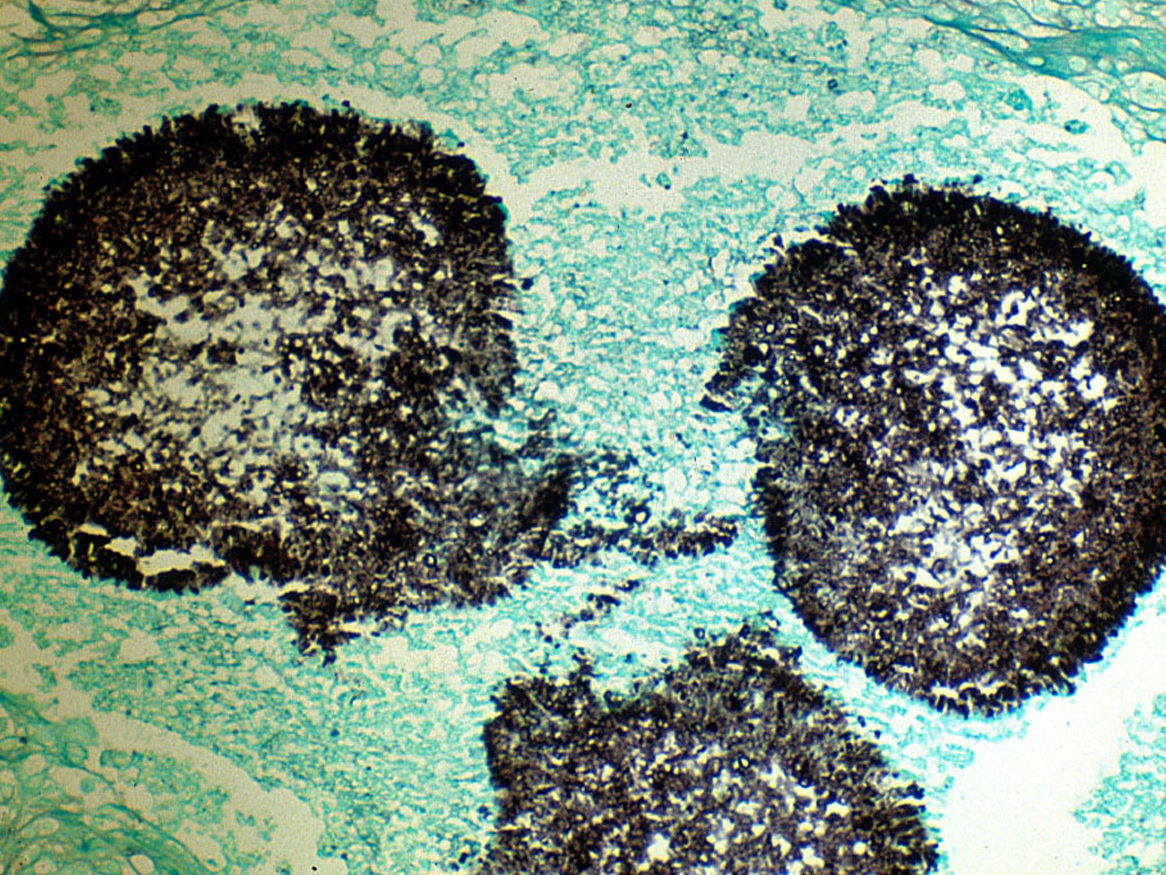

Визуализация и диагностика неинвазивного аспергиллеза с помощью КТ